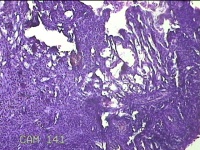

右侧卵巢囊肿

性别

女

年龄

36岁

临床诊断

一般病史

发现双侧附件囊肿1年。

标本名称

大体所见

灰白暗红色囊壁样组织2.5x2x0.3cm一块,表面光滑,部分已切开,囊内容物已流失,囊壁厚0.2cm。

考虑:子宫内膜异位囊肿。